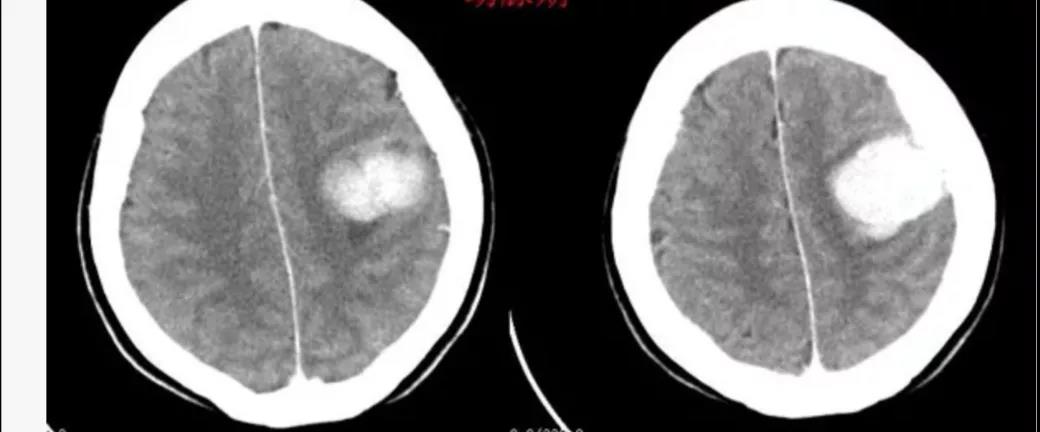

患者,58岁,渐进性头疼1年余,遂来我院就诊。入院后行头颅CT、MR示左侧顶叶占位性病变,经接诊医师李明详细说明病情后家属决定于我院进行手术治疗。

副主任周小荔积极组织全科医师慎密讨论,研究分析后认为病变系颅内重要功能区脑膜瘤。为避免损伤造成患者相关功能障碍,医师团队精心设计了手术方案,全面细致考虑了手术中可能出现的每一个环节,并进行了反复论证,最后确定了手术方案。明确手术方案后,由副主任医师李明主刀,主治医师谈小红、住院医师祁军强担任助手进行手术,肿瘤及被肿瘤侵蚀硬膜、颅骨成功切除,手术顺利。